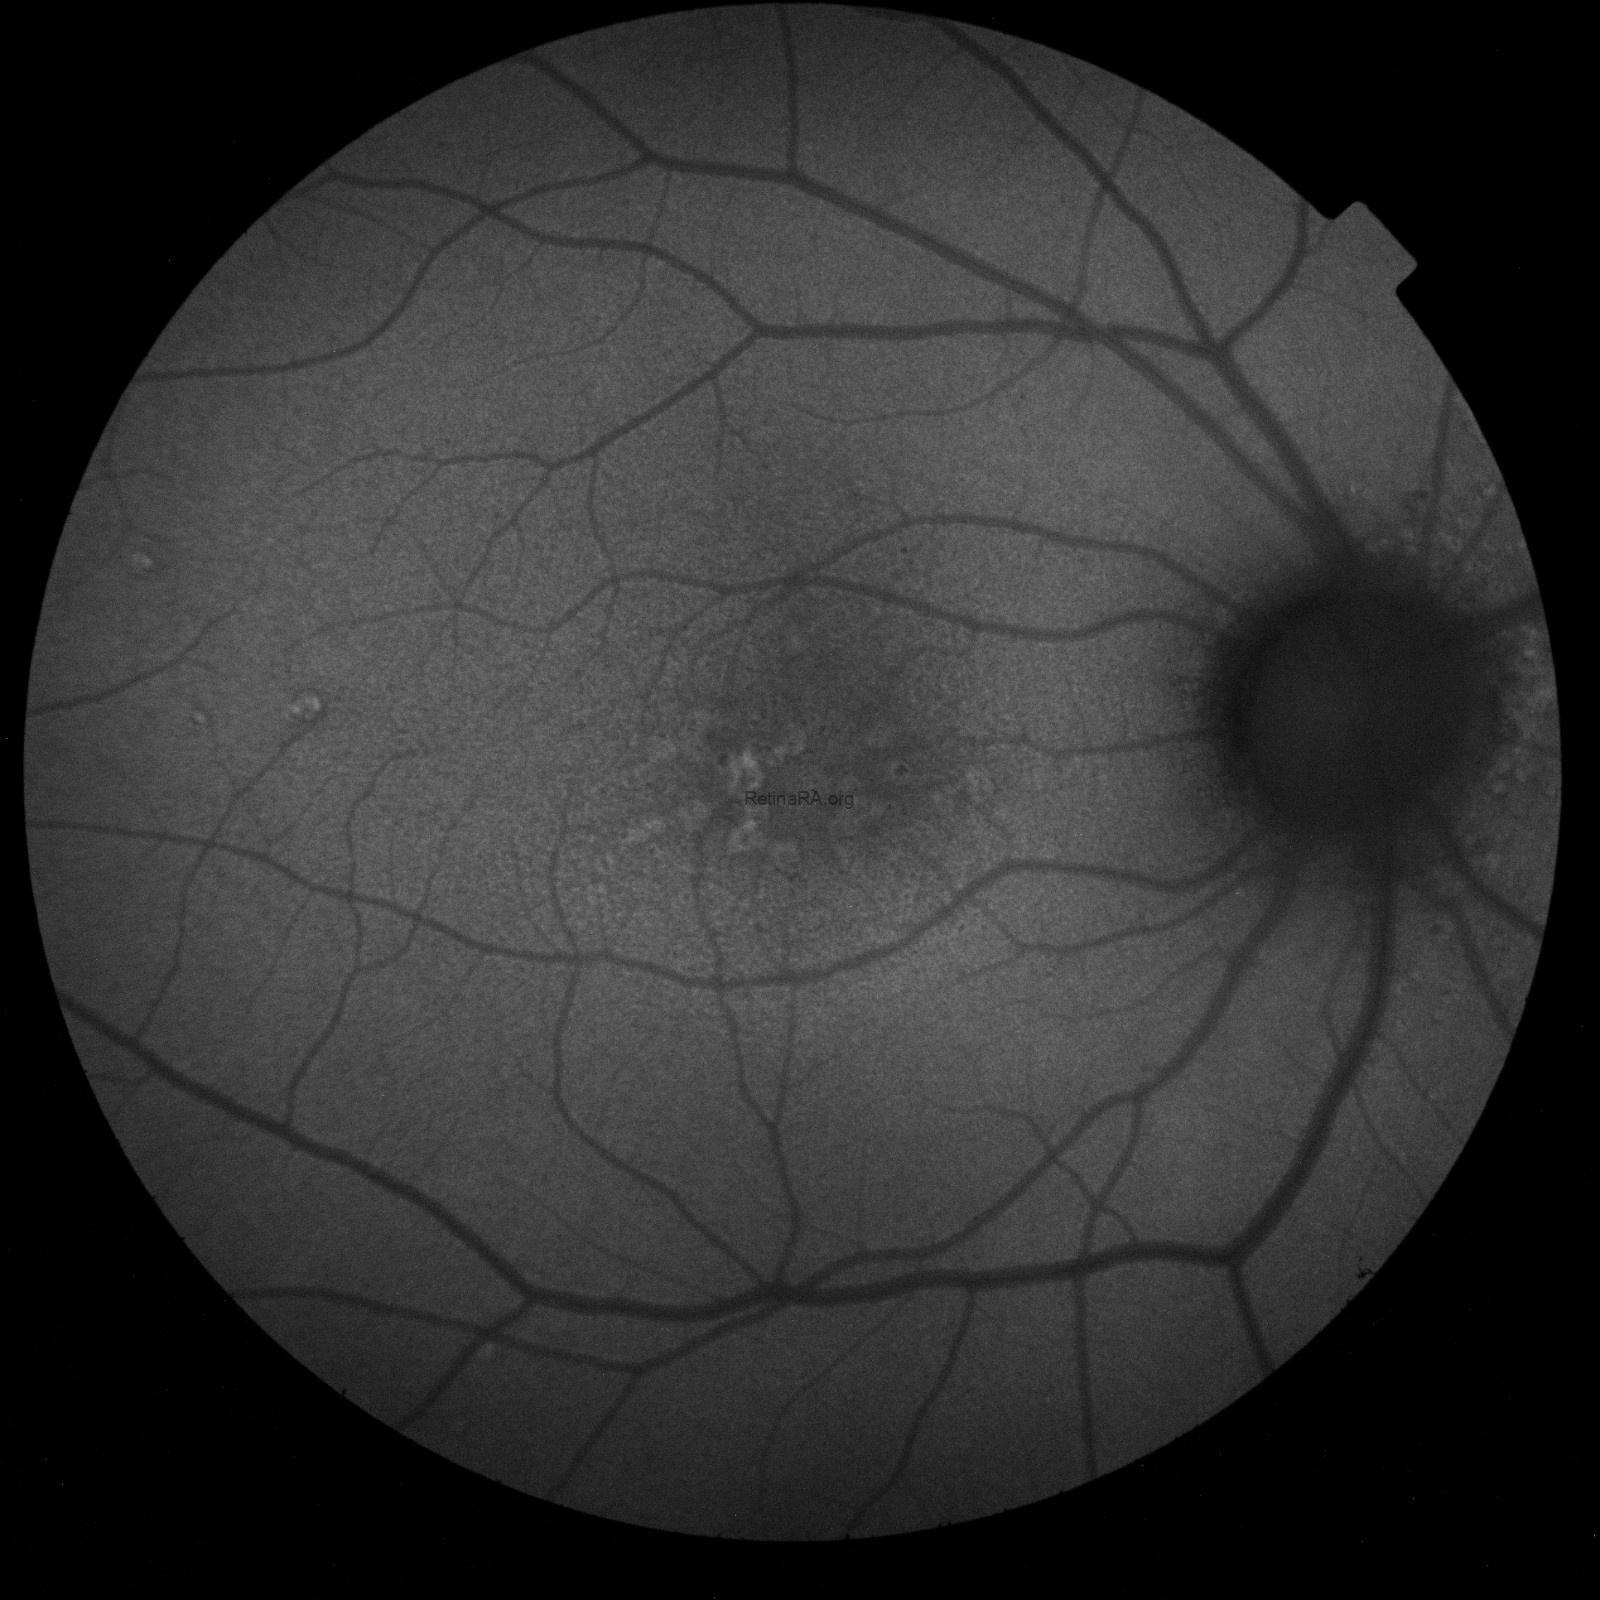

Fundus true-color photo shows multiple large yellowish drusen-like lesions scattered throughout the posterior pole and mainly clustered in the macular region in OU. On FAF, these lesions appear hyperautofluorescent with a surrounding hypoautofluorescent halo.

This correlates well with their appearance as shown on FAF, with a marked central hyperautofluorescence surrounded by a hypoautofluorescent halo, as well as en-face OCT, with a hyperreflective center bordered by a hyporeflective halo which, in turn, is surrounded by a hyper and a hypo-reflective ring.